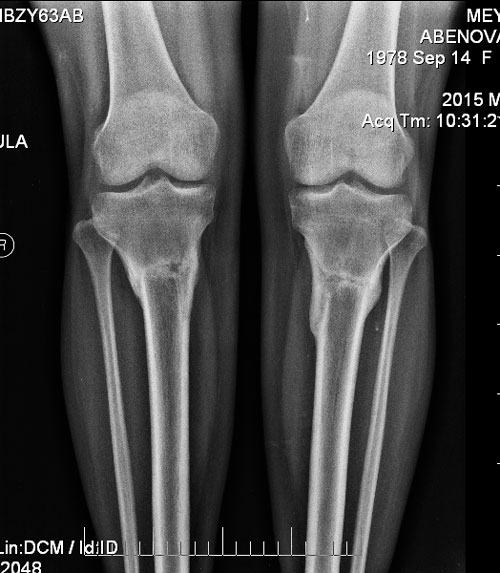

Ножки на сегодня.

Здравствуйте! По фото левая нога чуть тоньше правой. Присматриваемся, наблюдаем, не щадим, наступаем на обе ноги одинаково. Если будут сомнения, приезжайте!Добрый вечер.

Отправляю чуть раньше чем через две недели фото ног, так как появились сомнения насчет левой ноги. Как будто она изменилась, более Х-образной стала что ли. Посмотрите пж. Что скажите?